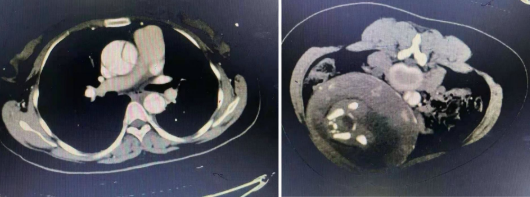

经过急诊行主动脉CTA显示,破口位于升主动脉根部,左冠开口受累,主动脉夹层A型。安医大一附院心脏大血管外科立即联合妇产科、输血科、麻醉科、心超室等相关科室,拟定手术方案。因为心脏手术会对胎儿产生非常大的影响,需要先进行剖宫产。12月15日一早,妇产科医师给予陈女士行剖宫产,顺利生下一名女婴。随即,心脏大血管外科葛圣林、冯俊波大血管团队行体外循环下深低温停循环下行主动脉瓣成形术+主动脉窦成形术+升主动脉部分切除伴人工血管置换术+全主动脉弓人工血管置换并支架象鼻手术。